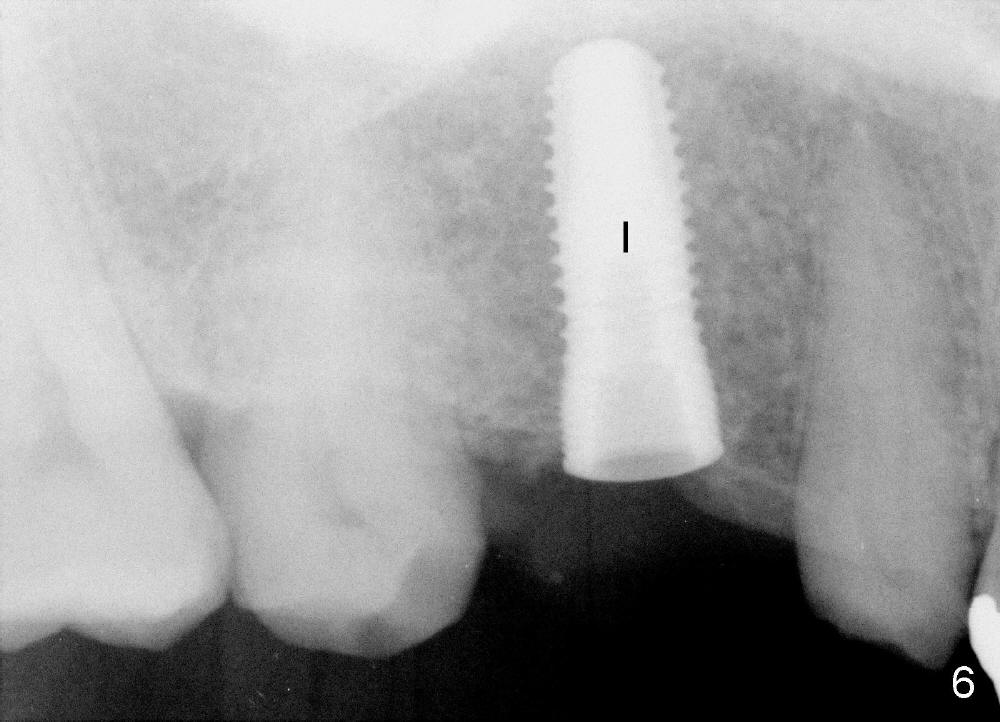

The bone density (Fig.1 white *) at the edentulous area (#3) is lower than that at the dentulous one (black *, 50 year-old man). The buccal plate is also atrophic and concave (Fig.2,3 arrowheads). A series of bone expanders are used to form osteotomy (following 1.6 mm pilot drill) at the depth of 14 mm (Fig.3 E 3.0 mm in diameter). When the last expander (4.3 mm) is removed from the osteotomy, the buccal plate appears to have been moved buccally (Fig.5 arrowheads). A 5.3x14 mm submerged implant (Fig.6 I) is placed with insertion torque >35 Ncm. The buccal plate seems to improve following placement of an 8.2 mm healing abutment and suturing (Fig.7). No bone graft is used. The buccal plate remains normal 12 days postop (Fig.8). It is slightly concave 3 months postop (Fig.9) with minimal bone resorption at the crest (Fig.10 (H: healing abutment),11 (A: cemented abutment). Nine months post cementation (12 months postop), bone resorption at the crest remains minimal (Fig.12) while the buccal plate (Fig.13 *) at #3 remains strong. Bone loss appears not to get worse 22 months post cementation (Fig.14). Soft and hard tissues remain healthy around the implant crown 3 years (Fig.15) and 3.5 years (Fig.16,17) post cementation.